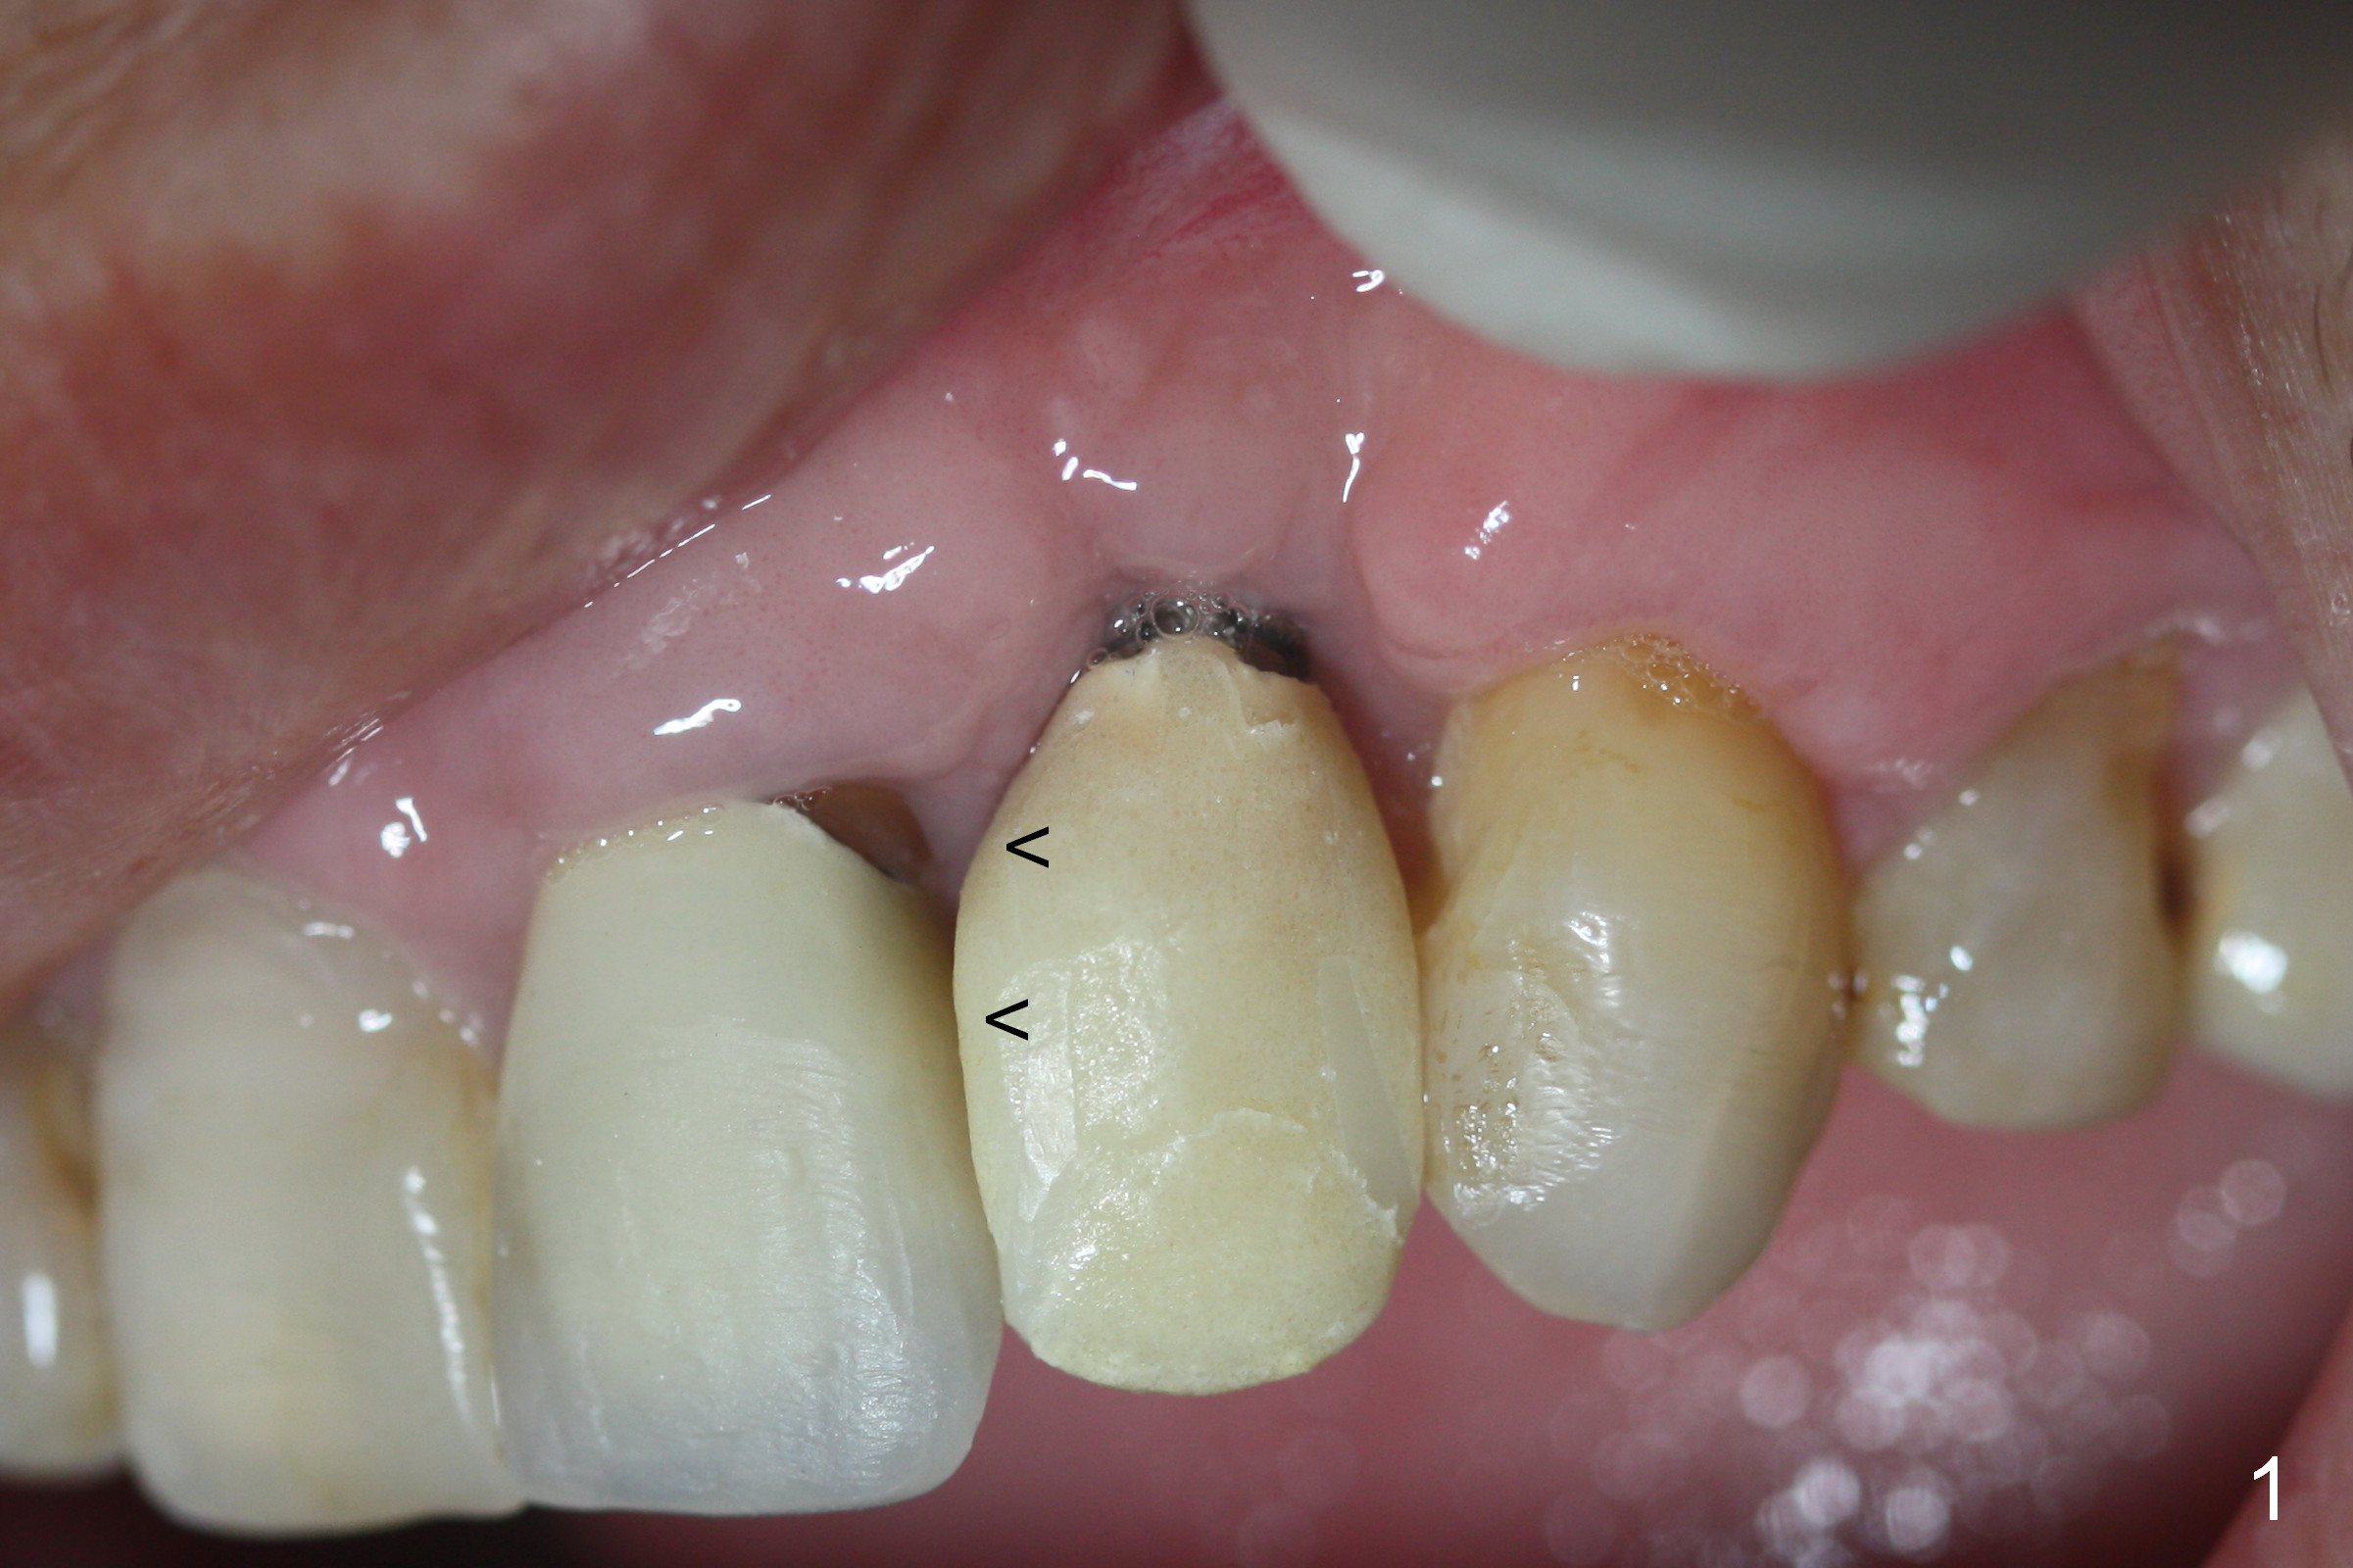

Mrs. Chen likes the shape of the temporary crown (Fig.1), particularly the mesial portion (arrowheads). Change the shape of the permanent crown (Fig.2 arrowheads) to alleviate the problem of papillary recession. Use the tooth #7 as a reference (Fig.3).